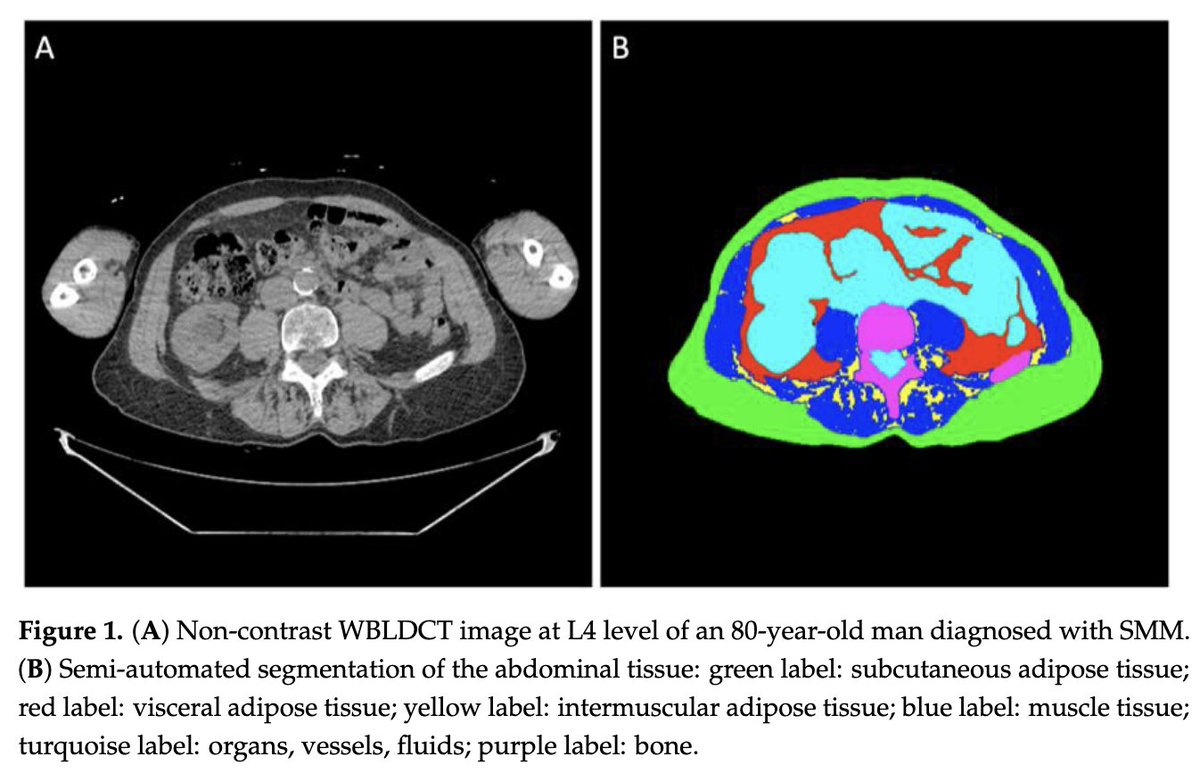

High subcutaneous adipose tissue (SAT) cross-sectional area (CSA) and high SAT index may both be associated with a lower progression risk from smoldering myeloma to clinically active myeloma.”

Title: Body Composition Metrics Associated with Time to Progression in Smoldering Multiple Myeloma